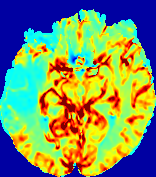

LesionRefer to captionRefer to captionRefer to captionRefer to captionRefer to captionRefer to caption𝐕rgbsubscript𝐕𝑟𝑔𝑏{\bf{V}}_{rgb}Refer to captionRefer to captionRefer to captionRefer to captionRefer to captionRefer to caption𝐕2subscriptnorm𝐕2{\|\bf{V}}\|_{2}Refer to captionRefer to captionRefer to captionRefer to captionRefer to captionRefer to captionRefer to caption3.53.53.52.82.82.82.12.12.11.41.41.40.70.70.70.00.00.0(mm/s)𝑚𝑚𝑠(mm/s)D𝐷DRefer to captionRefer to captionRefer to captionRefer to captionRefer to captionRefer to captionRefer to caption0.0200.0200.0200.0160.0160.0160.0120.0120.0120.0080.0080.0080.0040.0040.0040.0000.0000.000(mm2/s)𝑚superscript𝑚2𝑠(mm^{2}/s)Slice #1Slice #2Slice #3Slice #4Slice #5Slice #6

Figure 3: PIANO feature maps for one stroke patient, where the lesion is located in the left hemisphere. Top row: segmented stroke lesion region (white) on different slices, obtained from ISLES 2017. The corresponding slices for the PIANO feature maps are shown in the following rows.

For a better insight into an estimated velocity field 𝐕𝐕{\bf{V}} and diffusion field 𝐃𝐃{\bf{D}}, we compute the following maps: (1) 𝐕rgbsubscript𝐕𝑟𝑔𝑏{\bf{V}}_{rgb}: Color-coded orientation map of 𝐕=(Vx,Vy,Vz)T𝐕superscriptsuperscript𝑉𝑥superscript𝑉𝑦superscript𝑉𝑧𝑇{\bf{V}}=(V^{x},V^{y},V^{z})^{T}, obtained by normalizing 𝐕𝐕{\bf{V}} to unit length and mapping its 3 components to red, green, blue respectively; (2) 𝐕2subscriptnorm𝐕2\|{\bf{V}}\|_{2}: 222 norm of 𝐕𝐕{\bf{V}}; (3) D𝐷D: scalar field in Eq. 5.

Fig. 3 and Fig. 4 show the PIANO feature maps estimated from two ISLES 2017 patients: all are highly consistent with the lesion in both cases. Details of the blood flow trajectories are revealed in 𝐕rgbsubscript𝐕𝑟𝑔𝑏{\bf{V}}_{rgb} by the ridged patterns and the sharp changes of colors in the unaffected (right) hemisphere, while the flat patterns appearing within the lesion provide little directional information about the velocity and indicate low velocity magnitudes. Velocity magnitudes are more directly visualized via 𝐕2subscriptnorm𝐕2\|{\bf{V}}\|_{2}, from which one can easily locate the lesion where 𝐕2subscriptnorm𝐕2\|{\bf{V}}\|_{2} is low. D𝐷D also indicates lower diffusion values in the lesion, though with less contrast potentially due to the fact that it captures the accumulated effect of CA diffusion at the voxel-level.